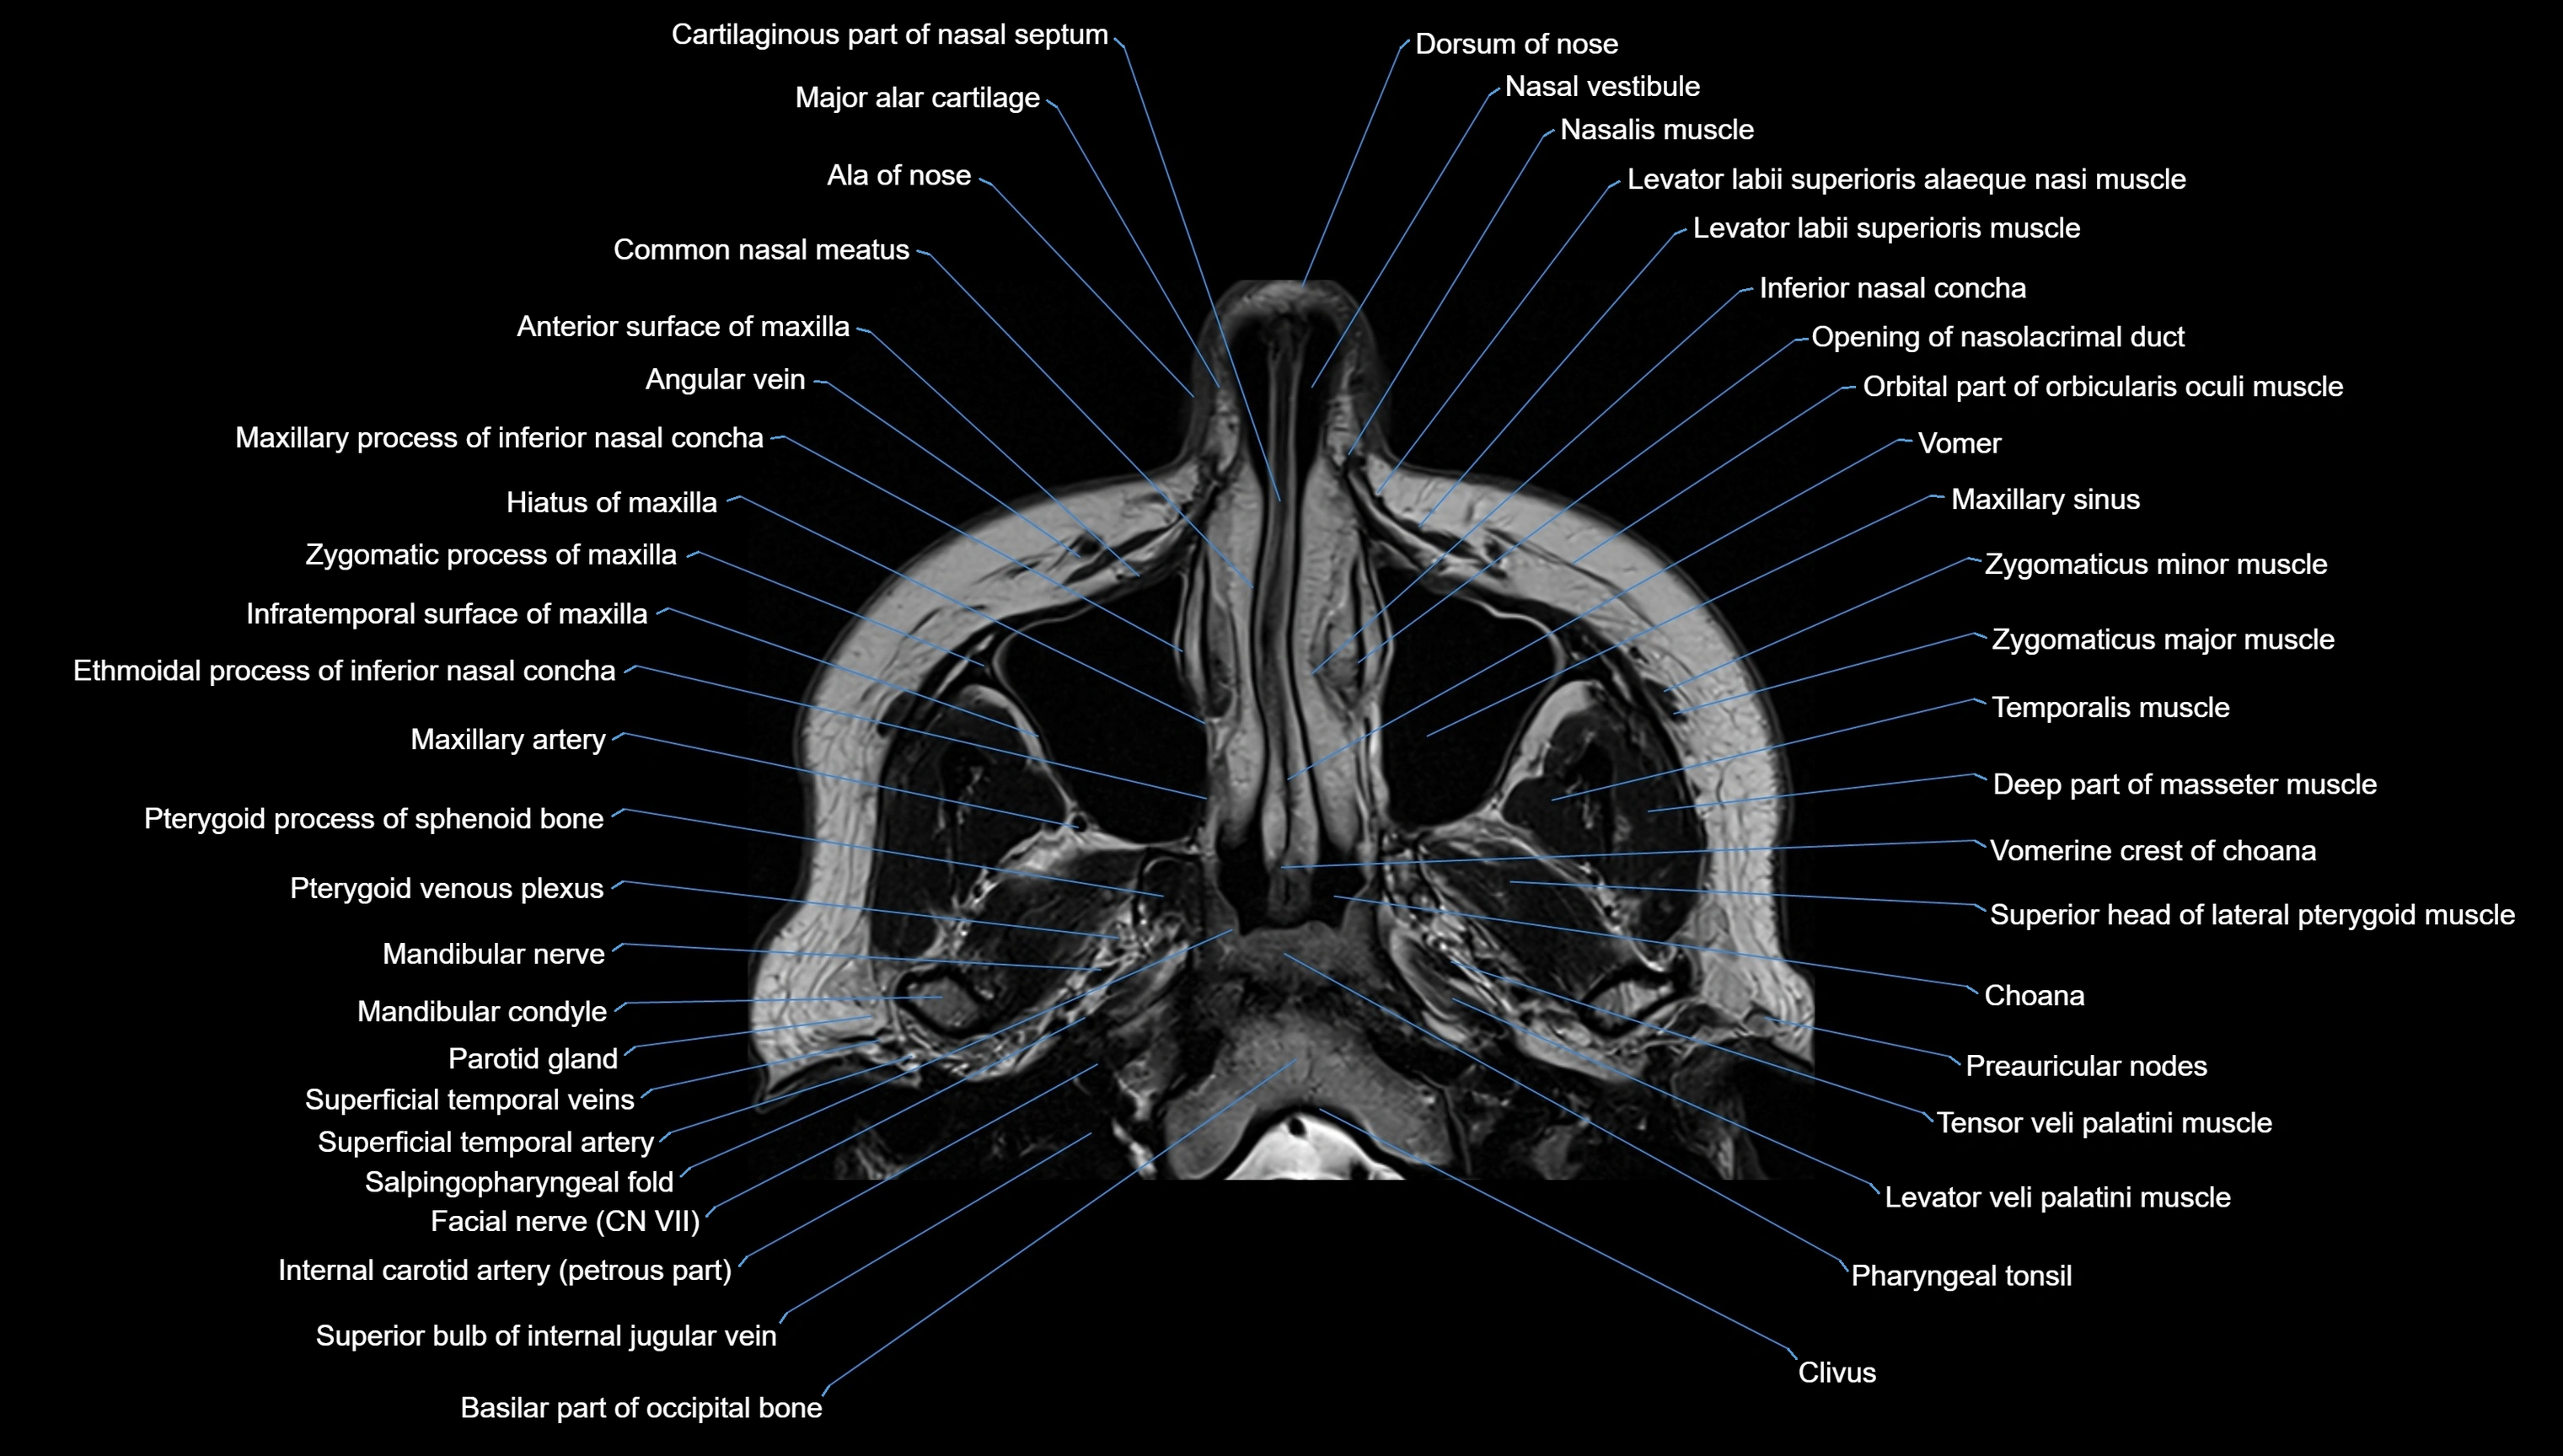

MRI images